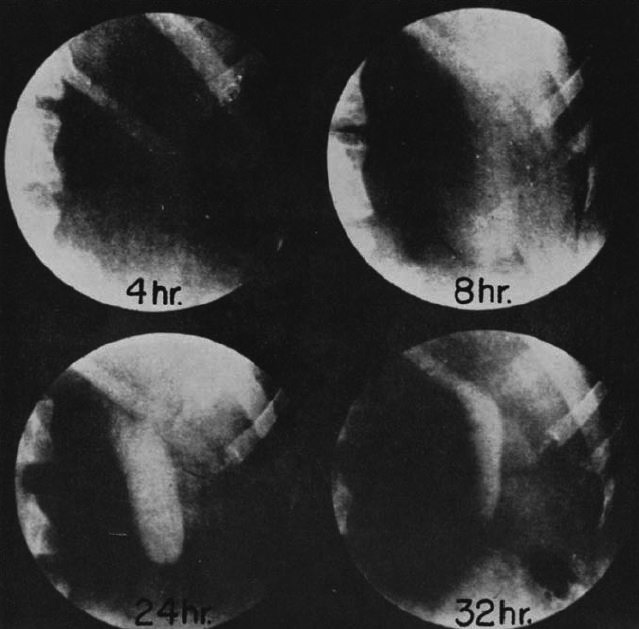

図2. 史上初のよる経静脈性胆嚢造影.四臭化フェノールフタレイン静注24時間後.

【要旨】肝機能検査薬として四塩化フェノールフタレインを使用した経験上,その大部分が胆汁中に排泄されることからこれを胆道造影剤として使用することを試み,動物実験を経て臨床例で初めて胆嚢造影に成功した.四塩化フェノールフタレインは造影効果が弱く,ヨウ化物は造影効果は良好だが副作用が強いことから,妥協案として四臭化フェノールフタレインを使用した.さらにナトリウム塩よりもカルシウム塩の方が造影効果が優れていることが判明した(図2).

この報告の3ヵ月後の第2報では,第1報で使用した四臭化フェノールフタレインのカルシウム塩は副作用が多いことからナトリウム塩に変え,症例を追加して報告するとともに,具体的な検査手順を明示している.朝食禁食として早朝に造影剤を静注,昼食も禁食として,3時間毎に重炭酸ナトリウムを服用し,4,8,24,32時間後にX線撮影を行なう.正常例では,4~8時間後から陰影が出現し,16~24時間でピーク濃度となり,48時間では消失する.病変のある胆嚢は,正常例のような濃い陰影がみられないか,あるいは造影されないとしている.

【解説】四臭化フェノールフタレインによる胆嚢造影の初報である.Grahamらは,この翌年に続報を発表しており[9],四臭化フェノールフタレインのナトリウム塩による造影55例中,13例に副作用(嘔気,嘔吐,各所の疼痛,血圧低下)が見られ,胆嚢炎の95%を正しく診断できたとしている.ただしこの診断は,第2報で述べられているように,胆嚢が良く見えれば正常,さもなければ異常という大ざっぱなものである.

初報に供覧されている2枚の臨床例のX線写真は,現在からみるといずれも不明瞭ではあるが,胆嚢をX線写真でとらえることができたことは,当時としては画期的なことであった.

図7. 史上初のヒトの胆嚢造影成功例.四臭化フェノールフタレイン静注24時間後(左下)で最も良好に造影されている.

【要旨・解説】1924年に初の胆嚢造影に成功した外科医,Warren H. Cole自身が,1960年の北米放射線学会(RSNA)でCarman記念講演*で発明の経緯を語った講演記録である.詳細な舞台裏が述べられており興味深い読み物となっている.

ここでは触れられていないが,当時1923年春,Coleはワシントン大学Graham教授の下の1年目外科レジデントで,7月から2年目はフルタイムで胆嚢造影の研究をするようにGrahamに命じられた[11].1910年にAbel & Rontree[6]が,下剤として研究していたフェノールフタレインの大部分が胆汁に排泄されることを発見したことから,Grahamはこれをハロゲン化してX線不透過性とすることにより胆嚢造影が可能と考え,その実験をColeに託した.早速7月から実験を開始したColeは,89種類のフェノールフタレイン化合物をイヌ,ウサギに投与し,最終的に四臭化フェノールフタレイン,四ヨウ化フェノールフタレインを選択した. 当初,200頭以上のイヌに造影剤を注射して一例も造影できなかったが,1923年11月,ついに1頭の造影に成功した.しかしその後,全く同じ条件で投与しても再現できず途方にくれたが,実験助手を問い詰めたところそのイヌだけ朝食を与え忘れていたことが判明し,造影に絶食が必要であることが分かった.1924年2月には,初の臨床例で造影に成功した(図7).